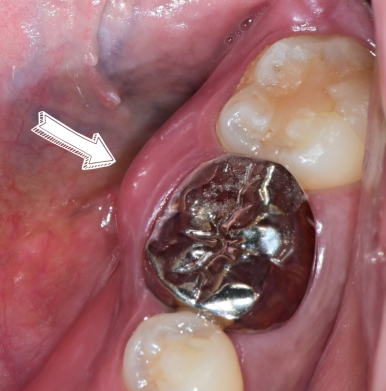

3. 급성 치주농양이 생긴 경우

통증이 심하고 잇몸에서 **고름(농)**이 나오는 경우에는 응급 배농이 우선입니다.

이후 원인인 치은연하 치석과 플라그까지 제거해야 염증이 반복되지 않습니다.